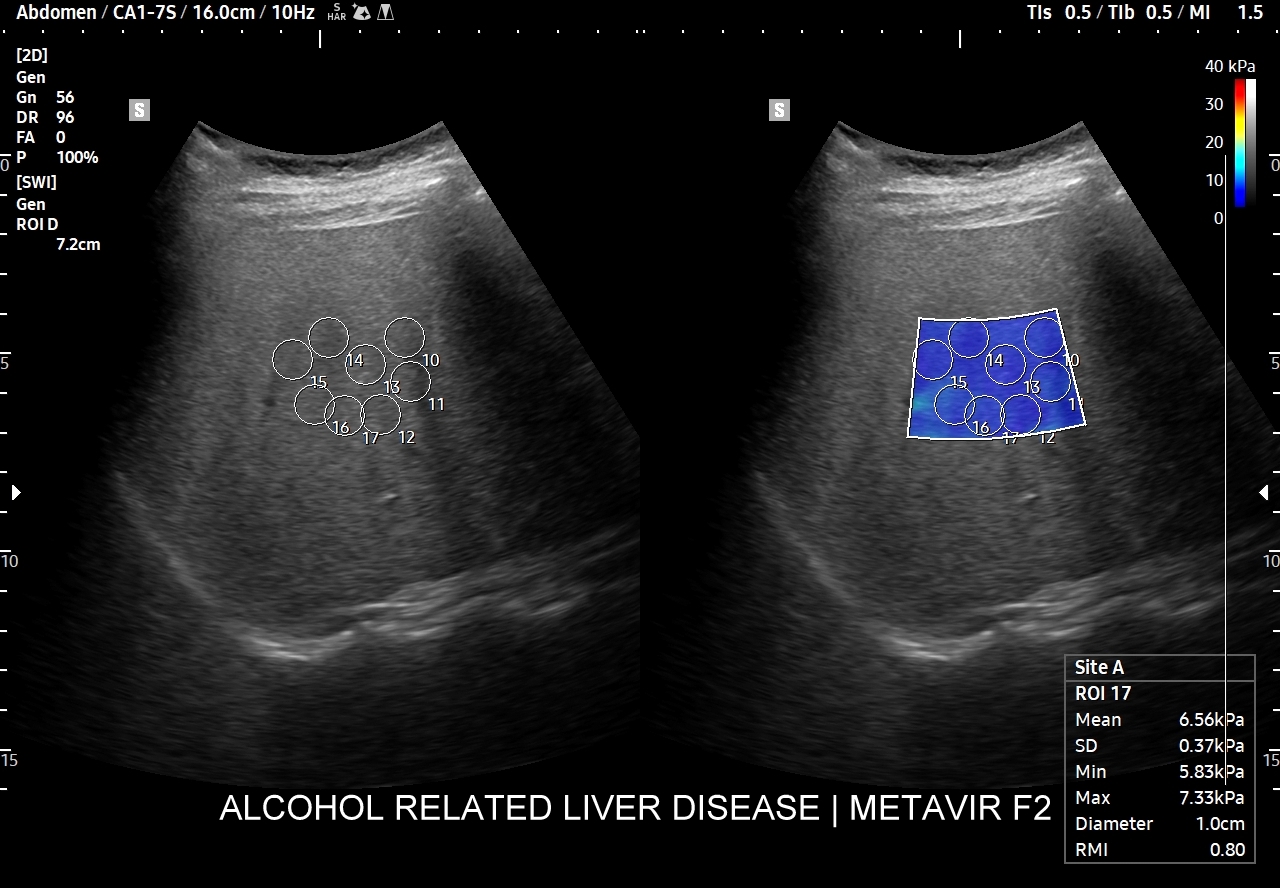

Otóż dokładne określenie stopnia zaawansowania zwłóknienia wątroby ma istotne znaczenie przy zaleceniach terapeutycznych, np. w przebiegu infekcji HBV i HCV. Metodą referencyjną oceny stopnia zwłóknienia wątroby jest biopsja narządowa z podaniem wyniku w histologicznej skali METAVIR, gdzie F0 oznacza prawidłowy obraz histopatologiczny miąższu, F1 minimalne zwłóknienie, F2 znaczne zwłóknienie; F3 zaawansowane zwłóknienie, a F4 marskość. Biopsja wątroby jednakże jako metoda inwazyjna ma swoje wady w postaci potencjalnych poważnych powikłań (np. krwiak, krwawienie do dróg żółciowych, zapalenie otrzewnej, zakażenie, posocznica, hemothorax). Poza tym próbka biopsyjna reprezentuje jedynie drobny ułamek całości objętości miąższu wątroby.

Z tego względu do określenia zwłóknienia wątroby poprzez ocenę jej sztywności obecnie częściej wykorzystuje się nieinwazyjne metody elastograficzne, wśród których najdokładniejszą jest 2D-SWE. Należy jednakże mieć na uwadze, iż ocena miąższu wątroby w technikach 2D-SWE nie jest jeszcze ostatecznie wystandaryzowana, a jednostkowe wartości odcięcia odpowiadające poszczególnym stadiom zwłóknienia mogą się różnić pomiędzy poszczególnymi dostępnymi komercyjnie systemami 2D-SWE.

Poniżej przedstawione są wartości odcięcia dla systemu 2D-SWE-SSI (Ferraioli et al., 2012): F2 – 7,1 kPa (1,50 m/s); F3 – 8,7 kPa (1,70 m/s); F4 – 10,4 kPa (1,90 m/s).

Dla ułatwienia oceny pomiarów a biorąc pod uwagę nakładanie się poszczególnych stopni zaawansowania zwłóknienia przy określonych wartościach sztywności wątroby rekomenduje się używanie neutralnej względem wszystkich dostępnych obecnie systemów elastograficznych tzw. reguły czwórek (ang. rule of four). Otóż sztywność wątroby równa lub mniejsza od 5 kPa (1,3 m/sek) oznacza z dużym prawdopodobieństwem brak zwłóknienia miąższu wątroby; sztywność do 9 kPa (1,7 m/sec) przy absencji innych objawów wyklucza skompensowaną zaawansowaną przewlekłą chorobę wątroby (cACLD, compensated advanced chronic liver disease); wartości wyższe od 13 kPa (2,1 m/sec) wskazują na cACLD.

Jak oceniać wątrobę w 2D-SWE? Badanie winno być wykonywane na czczo, na leżąco, przy spokojnym oddechu, poprzez przestrzenie międzyżebrowe w obrębie prawego płata wątroby. Bramki pomiarowe (ang. ROI) powinny być ustawiane w odległości minimum 1,5 – 2,0 cm od torebki wątroby oraz przy wspomaganiu mapą koloru w ten sposób, aby bramki ROI umieszczone zostały w obrębie obszaru z dominującym kolorem oraz w ten sposób, by unikać pojawiających się artefaktów. W przypadku 2D-SWE wystarczy 5-10 pomiarów wedle zasady, im większa wątpliwość lub rozbieżność, tym korzystniej zebrać jest ich więcej, np. 5 pomiarów przy IQR <15% lub 10 pomiarów przy IQR 15-30%.